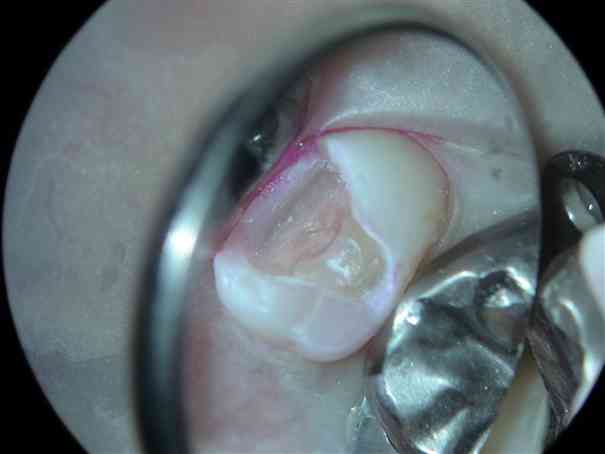

このように完全に神経が露出した場合でも、良く洗浄して、PROroot MTAを入れることによって神経を保存できます。PRO root MTAの歯髄保存効果はかなり高いといえます。ただ残念ながら、治療中にじわじわとした出血が認められる場合は歯髄の保存は不可能な場合が多いです。 |

別の症例ですが、 レジンインレーを取り除くと、中に茶色みがかった色の虫歯が認められます。この虫歯の場合相当深くなっていることが予想されます。 |